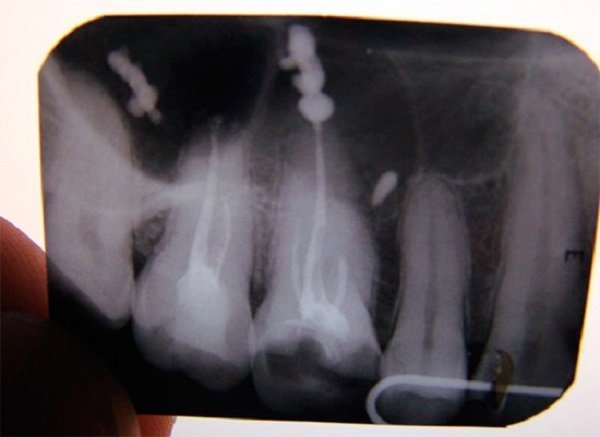

Обратитесь к стоматологу для рентгеновского снимка, чтобы определить точное расположение излишков пломбировочного материала.

Почему гуттаперча выходит за верхушку? Часть 1

Осложнения при лечении корня зуба

Как извлечь сломанный инструмент из корневого канала?

Осложнения при лечении пульпита. Попадание пломбировочного материала за пределы корня зуба

Какой силер лучше? Выход силера за верхушку. Силер в стоматологии